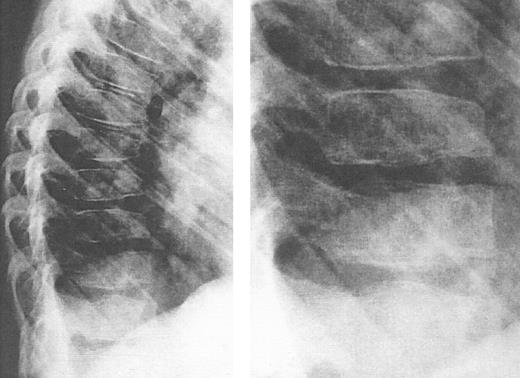

Adverse effects associated with deferoxamine include ocular and auditory abnormalities,225,227-235 sensorimotor neurotoxicity,236 changes in renal function,237,238 and pulmonary toxicity.239,240 A toxic manifestation of deferoxamine therapy of great concern in young children is failure of linear growth (Fig 7), associated with evidence of cartilagenous dysplasia of the long bones (Fig 8) and spine (Fig 9).141,142,241-247 Over the past 3 years, it has been recognized that short stature, primarily related to disproportionate truncal growth and loss of sitting height in thalassemic children,141,142 may be due to the effect of deferoxamine on spinal cartilage.244-246 At the same time, the findings of iron overload and hepatic damage in young transfused children outlined above have prompted our recommendations of the use of deferoxamine early in life, using reduced doses as a balance between risk and benefit. This practice is supported by studies of children who have received low-dose deferoxamine (15 to 35 mg/kg/night) since the age of 3 years, all of whom had normal sitting heights, standing heights, and normal spinal x-rays. By contrast, in a second cohort of children in which deferoxamine, administered at standard doses (50 mg/kg) from an equally early age had induced a comparable reduction in body iron burden, mean sitting height was markedly abnormal and significant x-ray abnormalities were observed.246 These data suggest that abnormal linear growth may be a direct toxic effect of prolonged administration of higher doses of deferoxamine, unrelated to changes in body iron. Because improvement in linear growth of patients with spinal abnormalities has not been observed even with reduction of deferoxamine dose, it would appear important to prevent this toxicity.

Lateral view of the thoracic spine in an 11-year, 9-month-old girl with thalassemia major treated with intensive deferoxamine throughout childhood. The spine shows decreased vertebral height with intervertebral disc calcification, flattening and lengthening and anterior tapering or the vertebrae, wedging and moderate kyphosis in this region. Detailed inset shows a bone-within-bone appearance, demarcating a zone of pronounced calicification. (Reprinted by permission from Pediatric Radiology, Spinal deformities in deferoxamine-treated beta-thalassemia major patients, Hartkamp MJ, Babyn PS, Olivieri NF, Volume 23, pp 525-528, Figure 2, 1993, Copyright Springer-Verlag GmbH & Co, KG. 1993.)244